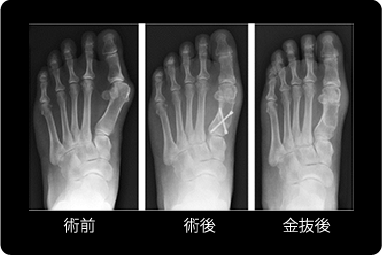

Hammond法

変形が比較的強い例に対して選択している手術方法です。

母趾の付け根の骨(第一中足骨)を遠位内側の出っ張りを削り、近位でドーム状に骨切りして矯正後に特殊なネジ2本で固定し、母趾内転筋(鼻緒をつまむ力の筋)を母趾の基節骨から切り離して、中足骨の頸部に開けたトンネルに通して固定します。

Hammond法の説明図